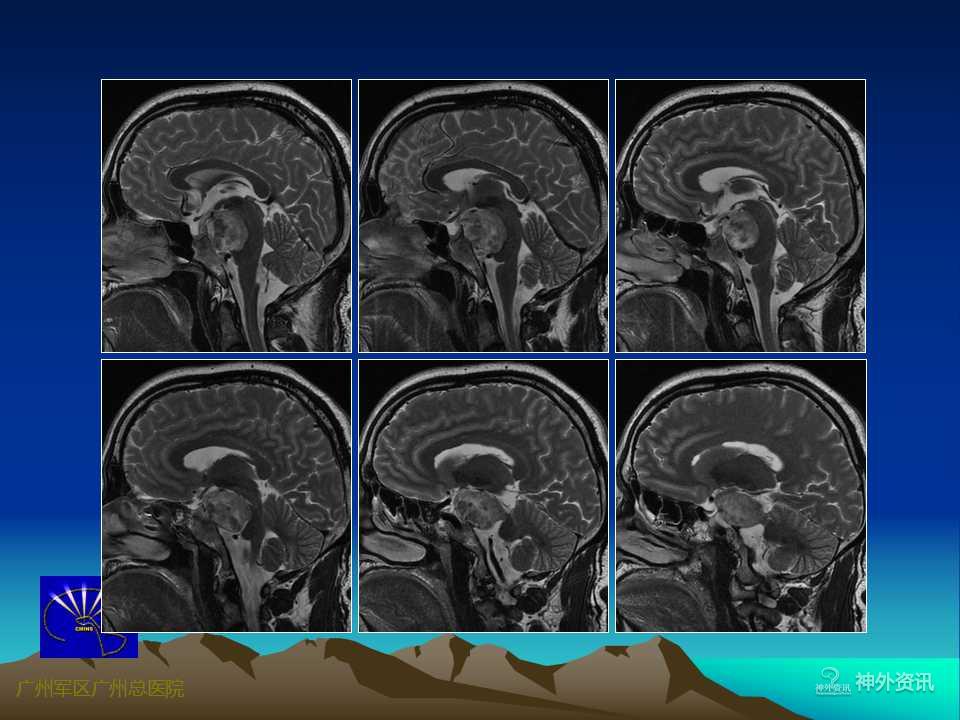

岩尖区是指从内听道到岩骨尖的这一狭小区域,毗邻海绵窦后壁,有岩上窦和岩下窦汇入,后方为脑干(中脑和脑桥)、基底动脉及其分支,邻近有Ⅲ~Ⅷ脑神经走行。岩尖区肿瘤常骑跨中、后颅窝及幕上、下两个颅区,与上述重要解剖结构紧密相邻或相连,手术难度较大,术后并发症相对较多。随着显微神经外科技术的不断发展和对该区域显微解剖结构认识的不断提高,目前该区域肿瘤手术的死亡和致残率已明显下降,但仍被认为是当前神经外科极具挑战性的手术之一。

岩尖区肿瘤以脑膜瘤最为常见,其次为神经鞘瘤、胆脂瘤等,由于脑膜瘤基底较宽,与其周围结构粘连较紧,故手术难度最大,且肿瘤是否侵及海绵窦是决定手术能否全切及影响手术预后的一个重要因素。岩尖区肿瘤的手术入路有多种,主要根据肿瘤的主体部位、侵及方向、供血特点以及毗邻结构等。可选择的手术入路有:经颅底岩斜区前方入路、侧方入路、后方入路、或幕上下联合入路等。

岩尖区肿瘤的手术入路较多,不同的手术入路有其各自的适用范围和不足之处。术前详尽的神经影像学检查对术前整体评估至关重要。将CT、CTA(含肿瘤组织、颅骨与血管的三维重建)、MRI、MRA等影像资料结合起来进行综合评判,充分了解肿瘤周围的解剖结构,特别是肿瘤的血供特点、与重要血管神经(脑神经)和脑干等的相互关系。DSA检查可明确肿瘤供血及周围血管移位情况。3D打印的出现使术者能够在3D打印模型上详细了解肿瘤的具体部位、大小、形态,肿瘤与其周围血管、脑干、脑神经、颅底等的相互关系,对指导手术入路、手术策略等具有极其重要的意义。随着人们对生活理念的改变,生存质量已备受重视。因此,目前对颅底肿瘤的手术已朝着简单、低侵袭性的方向发展,不再过分强调肿瘤的全切率,在保留重要神经血管功能的前提下最大限度地安全切除肿瘤、保证术后生活质量已成为广大神经外科医生和患者考虑的首要问题。